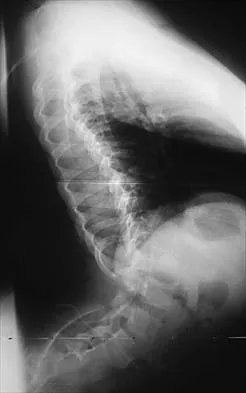

A 42-year-old man with a history of renal cell carcinoma has progressive weakness in the lower extremities for the past 3 weeks. The patient desires intervention. A sagittal T2-weighted MRI scan is shown in Figure 9a, and a sagittal contrast enhanced T1-weighted MRI scan is shown in Figure 9b. He currently ambulates minimal distances with a walker. His life expectancy is 8 months. Treatment of the spine lesion should consist of